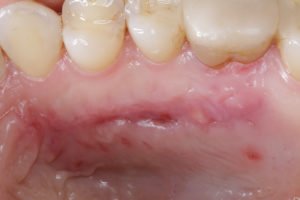

Figura 3 – A. Aspecto inicial do palato. Área doadora eleita para a remoção do ETCS. B. Após a remoção do ETCS pela técnica de bisturi de lâmina dupla descrita por Harris 1997. Na sequência,

depois de remover o enxerto para o fechamento da ferida, foi utilizado o fio de PTFE denso (Cytoplast – Osteogenics Biomedical) 4-0 com agulha de 13mm de comprimento, ½ de curvatura com o corte triangular reverso. C. Pós-operatório de sete dias. Imagem realizada antes da remoção do fio de sutura. Observar a ausência de acúmulo excessivo de biofilme bacteriano ao redor do fio de sutura. D. Pós-operatório de sete dias. Imagem realizada após a remoção do fio de sutura. Observar epitelização completa da ferida com pouca reação inflamatória tecidual proveniente do traumatismo do material de sutura e/ou do acúmulo do biofilme bacteriano. E. Pós-operatório de 14 dias após o procedimento cirúrgico. F. Pós-operatório de 30 dias após o procedimento cirúrgico. Observar o fechamento completo da ferida e ausência de reação inflamatória ou infecção no sítio doador.

Da mesma forma, as figuras 3C, D, E e F descrevem o processo de cicatrização da ferida cirúrgica palatina (área doadora). Podemos observar na figura 3C o pós-operatório de sete dias ainda com a presença do fio de sutura de PTFE denso.

Podemos observar, neste período, a ausência de grande quantidade de biofilme bacteriano ao redor do fio. Este aspecto tem um impacto clínico importante, uma vez que minimiza o risco de infecções e da formação de abcessos. Podemos notar também que o material de sutura neste período não perdeu a sua função primária de estabilização dos bordos da ferida indicando que não houve a perda da função do material. A figura 3D demonstra o pós-operatório de sete dias após a remoção do material de sutura. A figura 3E e F demonstram o pós-operatório de 14 e 30 dias

respectivamente. Observar a epitelização completa da ferida com ausência de processo infeccioso e abcessos.